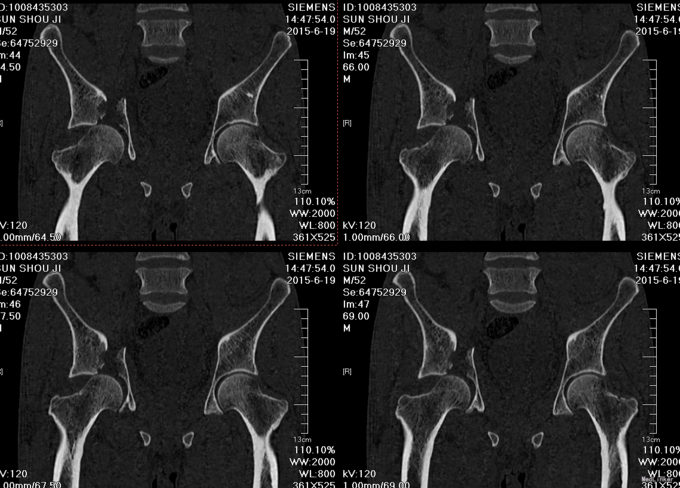

患者于2015年6月10日因车祸摔伤右侧髋关节,出现右髋部疼痛及活动受限。疼痛于活动后加重,休息可稍缓解。后就诊于营口市中心医院行骨盆三维CT示“右髋臼粉碎性骨折”,建议手术治疗,给予胫骨结节骨牵引术,患者于6月17日收入我院运动关节科病房,于6月19日转入我科。

患者入院后急诊行右髋关节脱位手法复位术,右胫骨结节骨骼牵引术。术后患者骨骼牵引约8公斤,术后约一星期后择期行右髋关节骨折切开复位钢板内固定书,术后患者病情平稳,术后三天转入当地医院继续治疗。